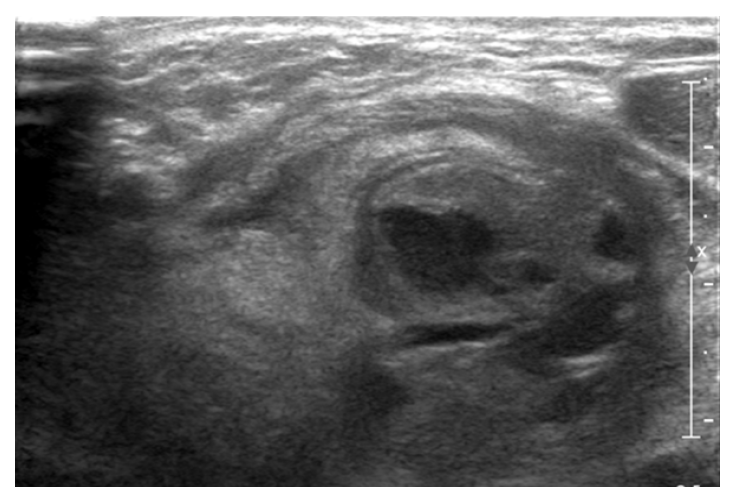

Neck ultrasonography. Probable abscess and phlegmonous

change in the lower poles of the left lobe of the thyroid

gland.